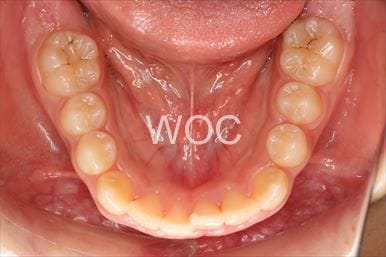

治療後1

治療後2

治療後3

治療後4

治療後5

- 年齢:20歳女性

- 主訴:出っ歯が気になる

- 基本矯正料金:120万円

- 治療期間:1年7ヶ月

- 抜歯部位:上顎両側第一小臼歯